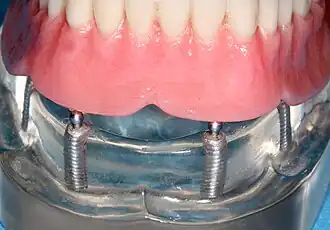

Four mandibular implants

Four lower implants to retain a complete denture with novaloc abutments

lower denture implant housing

Underside of a denture; housing fits like a ball and socket to hold the denture

Panorex radiograph showing implants

Xray of four Straumann implants and abutments

When a removable denture is worn, retainers to hold the denture in place can be either custom made or "off-the-shelf" (stock) abutments. When custom retainers are used, four or more implant fixtures are placed and an impression of the implants is taken and a dental lab creates a custom metal bar with attachments to hold the denture in place. Significant retention can be created with multiple attachments and the use of semi-precision attachments (such as a small diameter pin that pushes through the denture and into the bar) which allows for little or no movement in the denture, but it remains removable.[30]:33–34 However, the same four implants angled in such a way to distribute occlusal forces may be able to safely hold a fixed denture in place with comparable costs and number of procedures giving the denture wearer a fixed solution.[79]